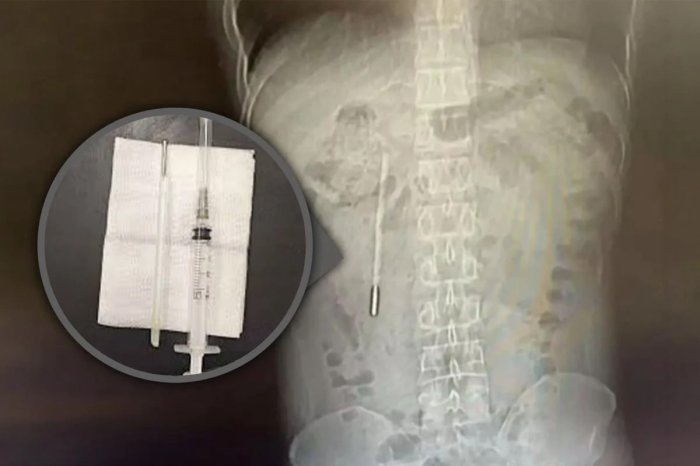

Китаец двадцать лет прожил с ртутным градусником в кишечнике

32-летний мужчина обратился в больницу с сильной болью в животе.

Выяснилось, что термометр он случайно проглотил ещё в детстве, но побоялся рассказать родителям и со временем просто забыл об этом.

По данным врачей, предмет начал давить на ткани, создавая риск внутреннего кровотечения.

Градусник успешно извлекли во время операции.